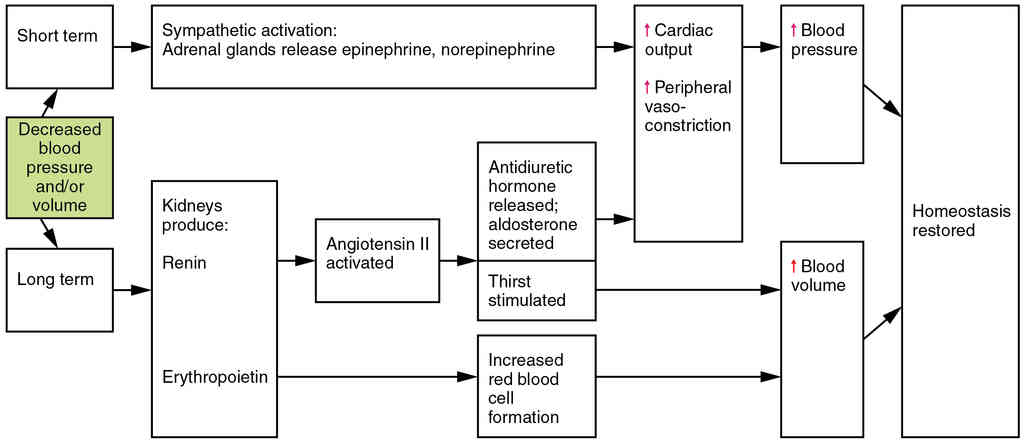

This page is under construction. For now, it is just a resource of the images found in the OpenStax Anatomy and Physiology Handbook. It wil slowly change into a revision tool. Each slide has a number. Use this to refer to the slide. When completed, it will have an unlabelled section, with labelled slides in parallel. On the unlabelled slides, write your answer and use the labelled slide to assess yourself. Keep track by also noting the number on each slide. Improvement at each attempt is important, more so than full marks on a first attempt.